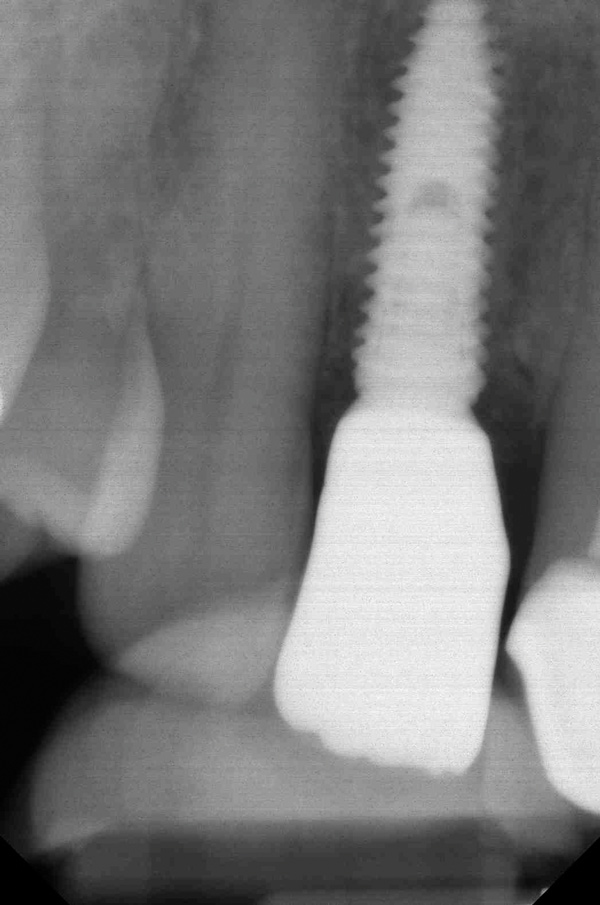

When placing an implant in the esthetic zone, ideal 3-dimensional positioning, including mesio-distal, apico-coronal, and orofacial dimensions, is essential to achieve favorable esthetic outcomes, regardless of the implant system used (Figure 6).45 With respect to the orofacial dimension, implants should be placed in a more palatal or lingual position to allow the presence of at least 2 mm of buccal bone thickness from the implant buccal shoulder.45,46 When the distance of the buccal bone wall and implant buccal shoulder is < 2 mm, a significantly higher incidence of midfacial recession has been previously reported.3,12 Placement of bone graft (Figure 7) and immediate restoration (Figure 8 and Figure 9) at the time of implant placement has also been suggested to increase peri-implant soft-tissue height and thickness.51 In the apico-coronal dimension, the implant head should be at least 3 mm apical to an imaginary line connecting the CEJ of the adjacent teeth and 1 mm to 2 mm apical to the interproximal and crestal bone to ensure a proper implant emergence profile and facilitate proper implant restoration (Figure 10). Regarding the horizontal implant–tooth distance, implants should be placed no closer than 1.5 mm from the adjacent root surface to minimize resorption of the interproximal alveolar crest, which causes a reduction in the papillary height.46,52